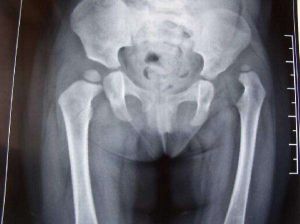

將寶寶帶到當地醫院的骨科就診,攝片大都可確診。如果父母粗心的話,待患兒開始走路(較同齡兒晚),如果是雙側脫位則出現“鴨步”,單側脫位則為搖擺跛行。大粗隆部突出,腰前凸增大,肢體短縮更為明顯。這時應儘早行手法復位外固定,以免軀體的缺陷的發生,影響到患兒的心理健康,婚姻及事業的發展,留下終身的遺憾。

先天性髖關節脫位的治療效果與年齡有很大的關係。發現越早,治療越及時,往往效果越好。一般來講,3歲以內的患兒主要採用牽引、手法復位、石膏及支具等保守治療,有很高治癒率;3歲以上的患兒,隨著年齡的增長,股骨頭和髖臼的骨性成份增加,內收肌的攣縮明顯,可塑性減少,病理變化加重,則以手術治療為主,雖經正確治療,功能難於達到正常。

出生至1歲是非手術治療的最佳時期。如能作到早期診斷和早期治療臨床效果是滿意的,如果延誤治療,最終將導致不可逆的痛性骨關節炎和不同程度的殘廢。